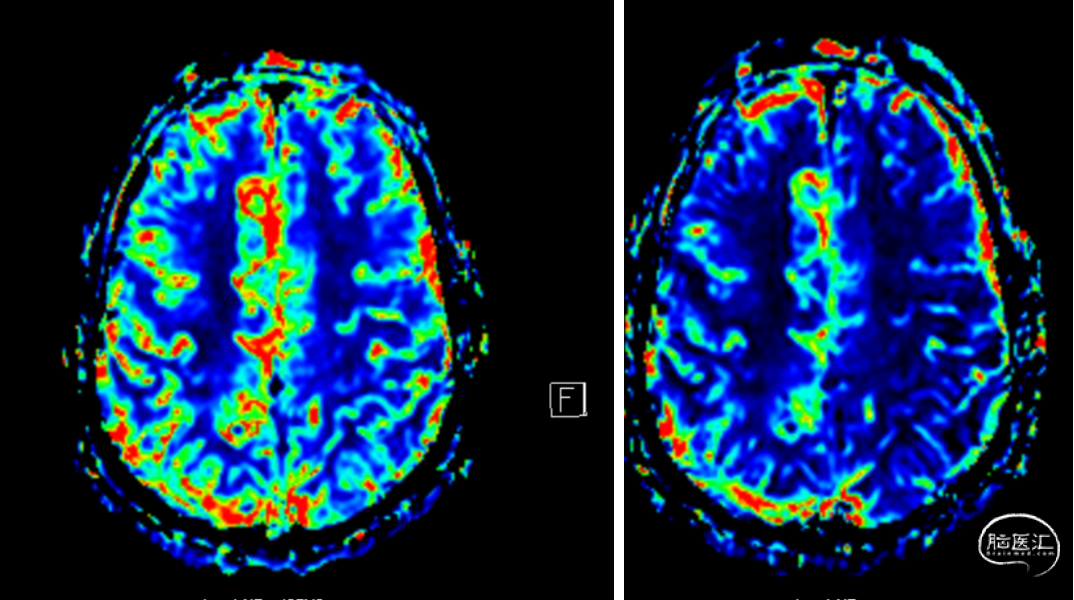

T2灌注增强扫描示:右侧额颞顶叶局部灌注异常,MTT、TTP延长,CBF、CBV示右侧颞叶局部区域稍减低。余脑实质未见异常灌注征象。